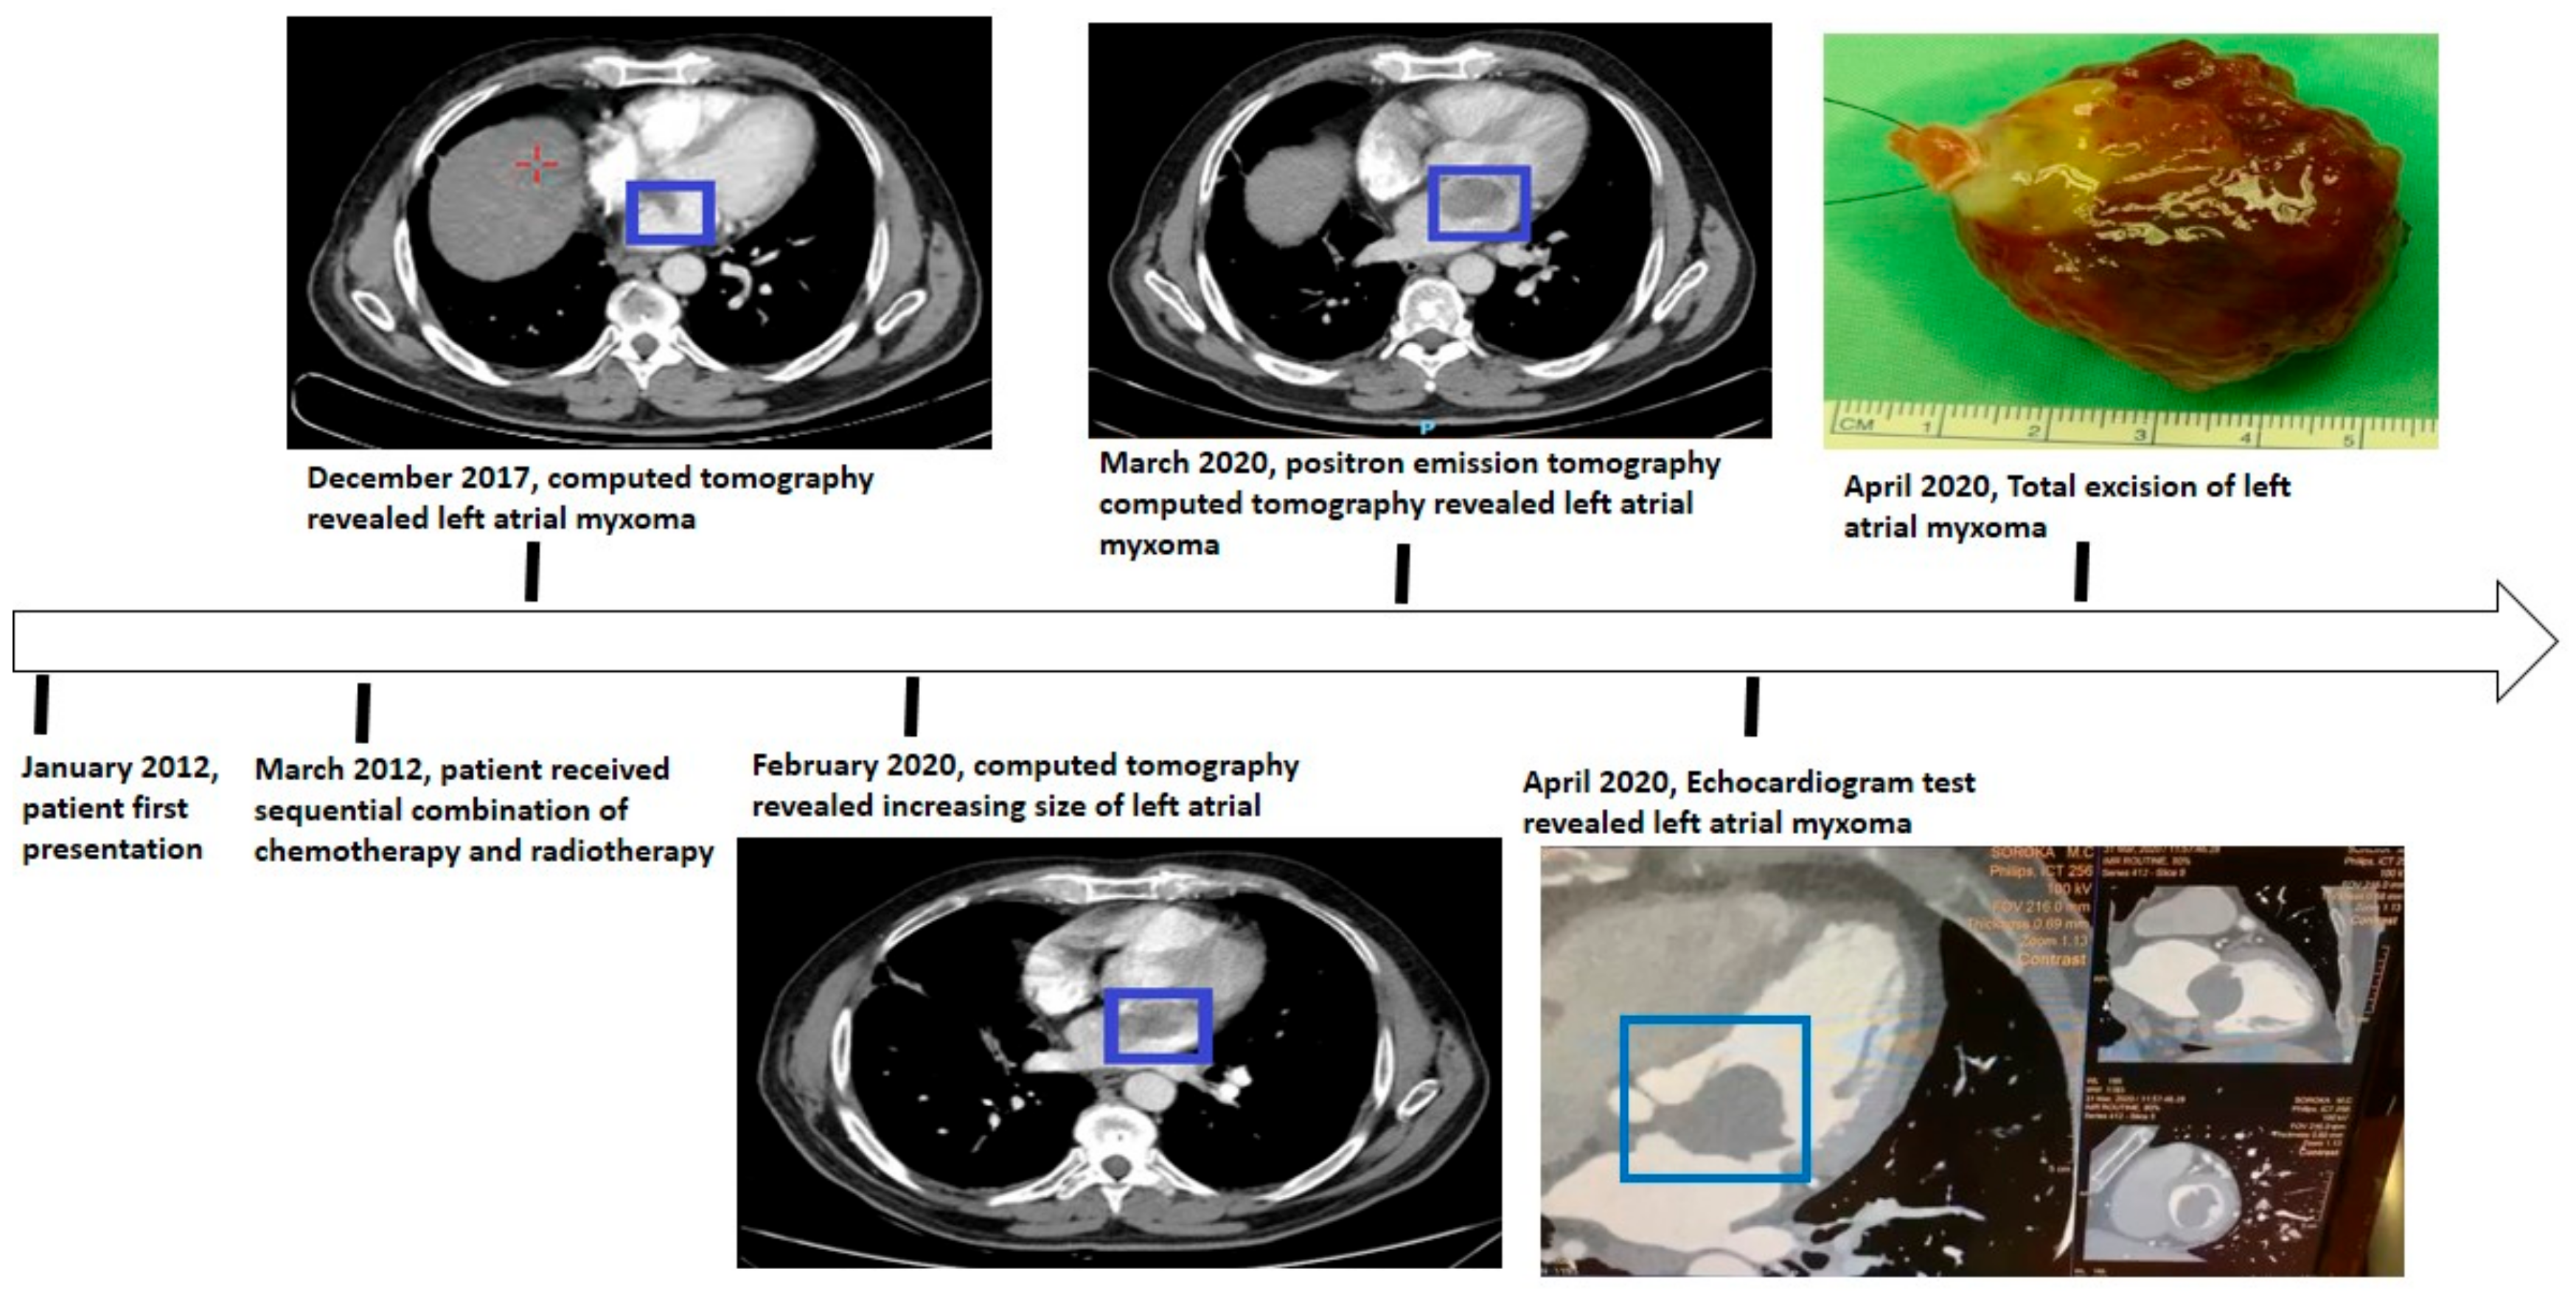

According to our patient, eight years prior to the diagnosis of the atrial myxoma, he had undergone concurrent chemo-radiotherapy (the accepted and recommended approach for stage 3 NSCLC [14]), which resulted in a complete response of the locally advanced lung cancer (Figure 5).

Figure 5.

A schematic illustration of the patient timeline from January 2012 (diagnosis of the disease) to April 2020 (the excision of the myxoma (blue square)).